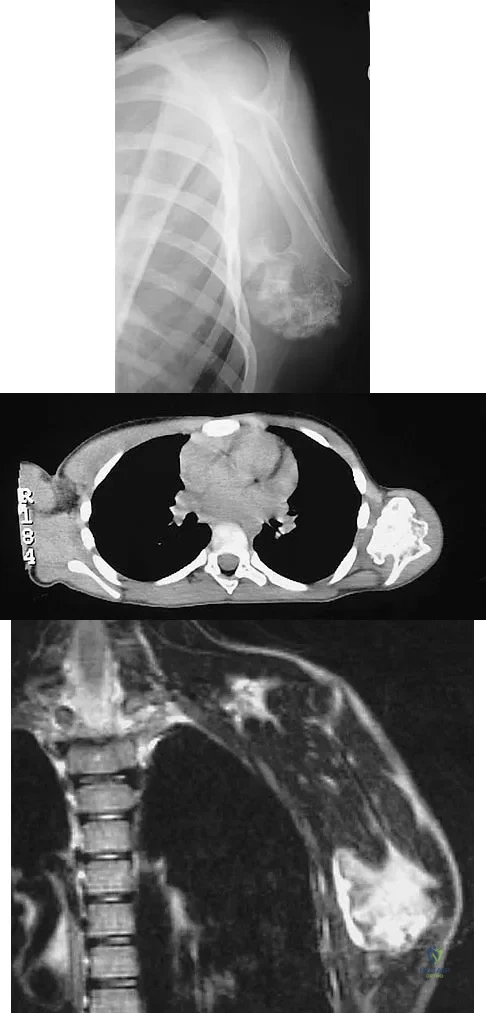

An otherwise healthy 75-year-old man has a painful mass in the popliteal fossa of his right knee. A lateral radiograph of the knee, a CT scan of the distal femur, and a histopathologic specimen are shown in Figures 13a through 13c. Management should consist of

Explanation